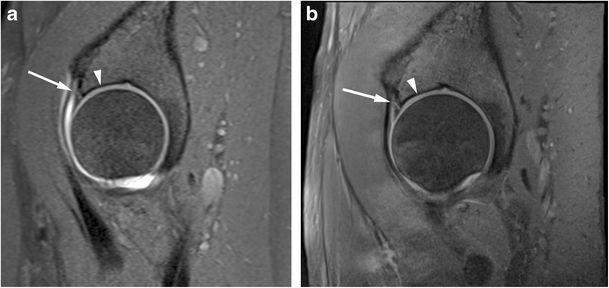

figure 6

Superior acetabular cartilage delamination in a 31-year-old confirmed at surgery. Coronal (a) T1 FS 1.5T MRA image shows intact superior labrum and the adjacent cartilage was scored by both readers as normal. (b) PD FS 3T MR image shows intact superior labrum and the adjacent cartilage was scored by both readers as low T1 signal indicating delamination

Recognising acetabular cartilage delamination is important as joint-preserving surgery can be attempted leading to symptomatic relief and improved prognosis [25]. Detection often relies on the presence of a fluid cleft between the cartilage and subchondral plate. This can be challenging due to the closely opposed articular surfaces which can effectively ‘close off’ the cleft, and it is thought arthrographic contrast should improve the detection by contrast flowing into this deep layer. Pfirrmann et al. retrospectively evaluated 1.5T MRA for cartilage delamination [16] and found that a fluid cleft was specific but insensitive for delamination, but hypointensity of articular cartilage on intermediate weighted fat-saturated and T1 sequences could be a helpful indicator of delamination (sensitivity 74 % and specificity 90 % for their most experienced reader). Conversely, Linda et al. found discordance between conventional 3T MRI and surgical findings for the assessment of cartilage delamination to be more marked than for other features of chondral damage [5]. We also found a low overall detection rate for both readers, evaluating for fluid and/or chondral hypointensity with low sensitivities using 1.5T MRA and conventional 3T MRI with better interobserver agreement for 1.5T MRA, but no statistically significant difference between the two (Table 4, Figs. 3 and 6).